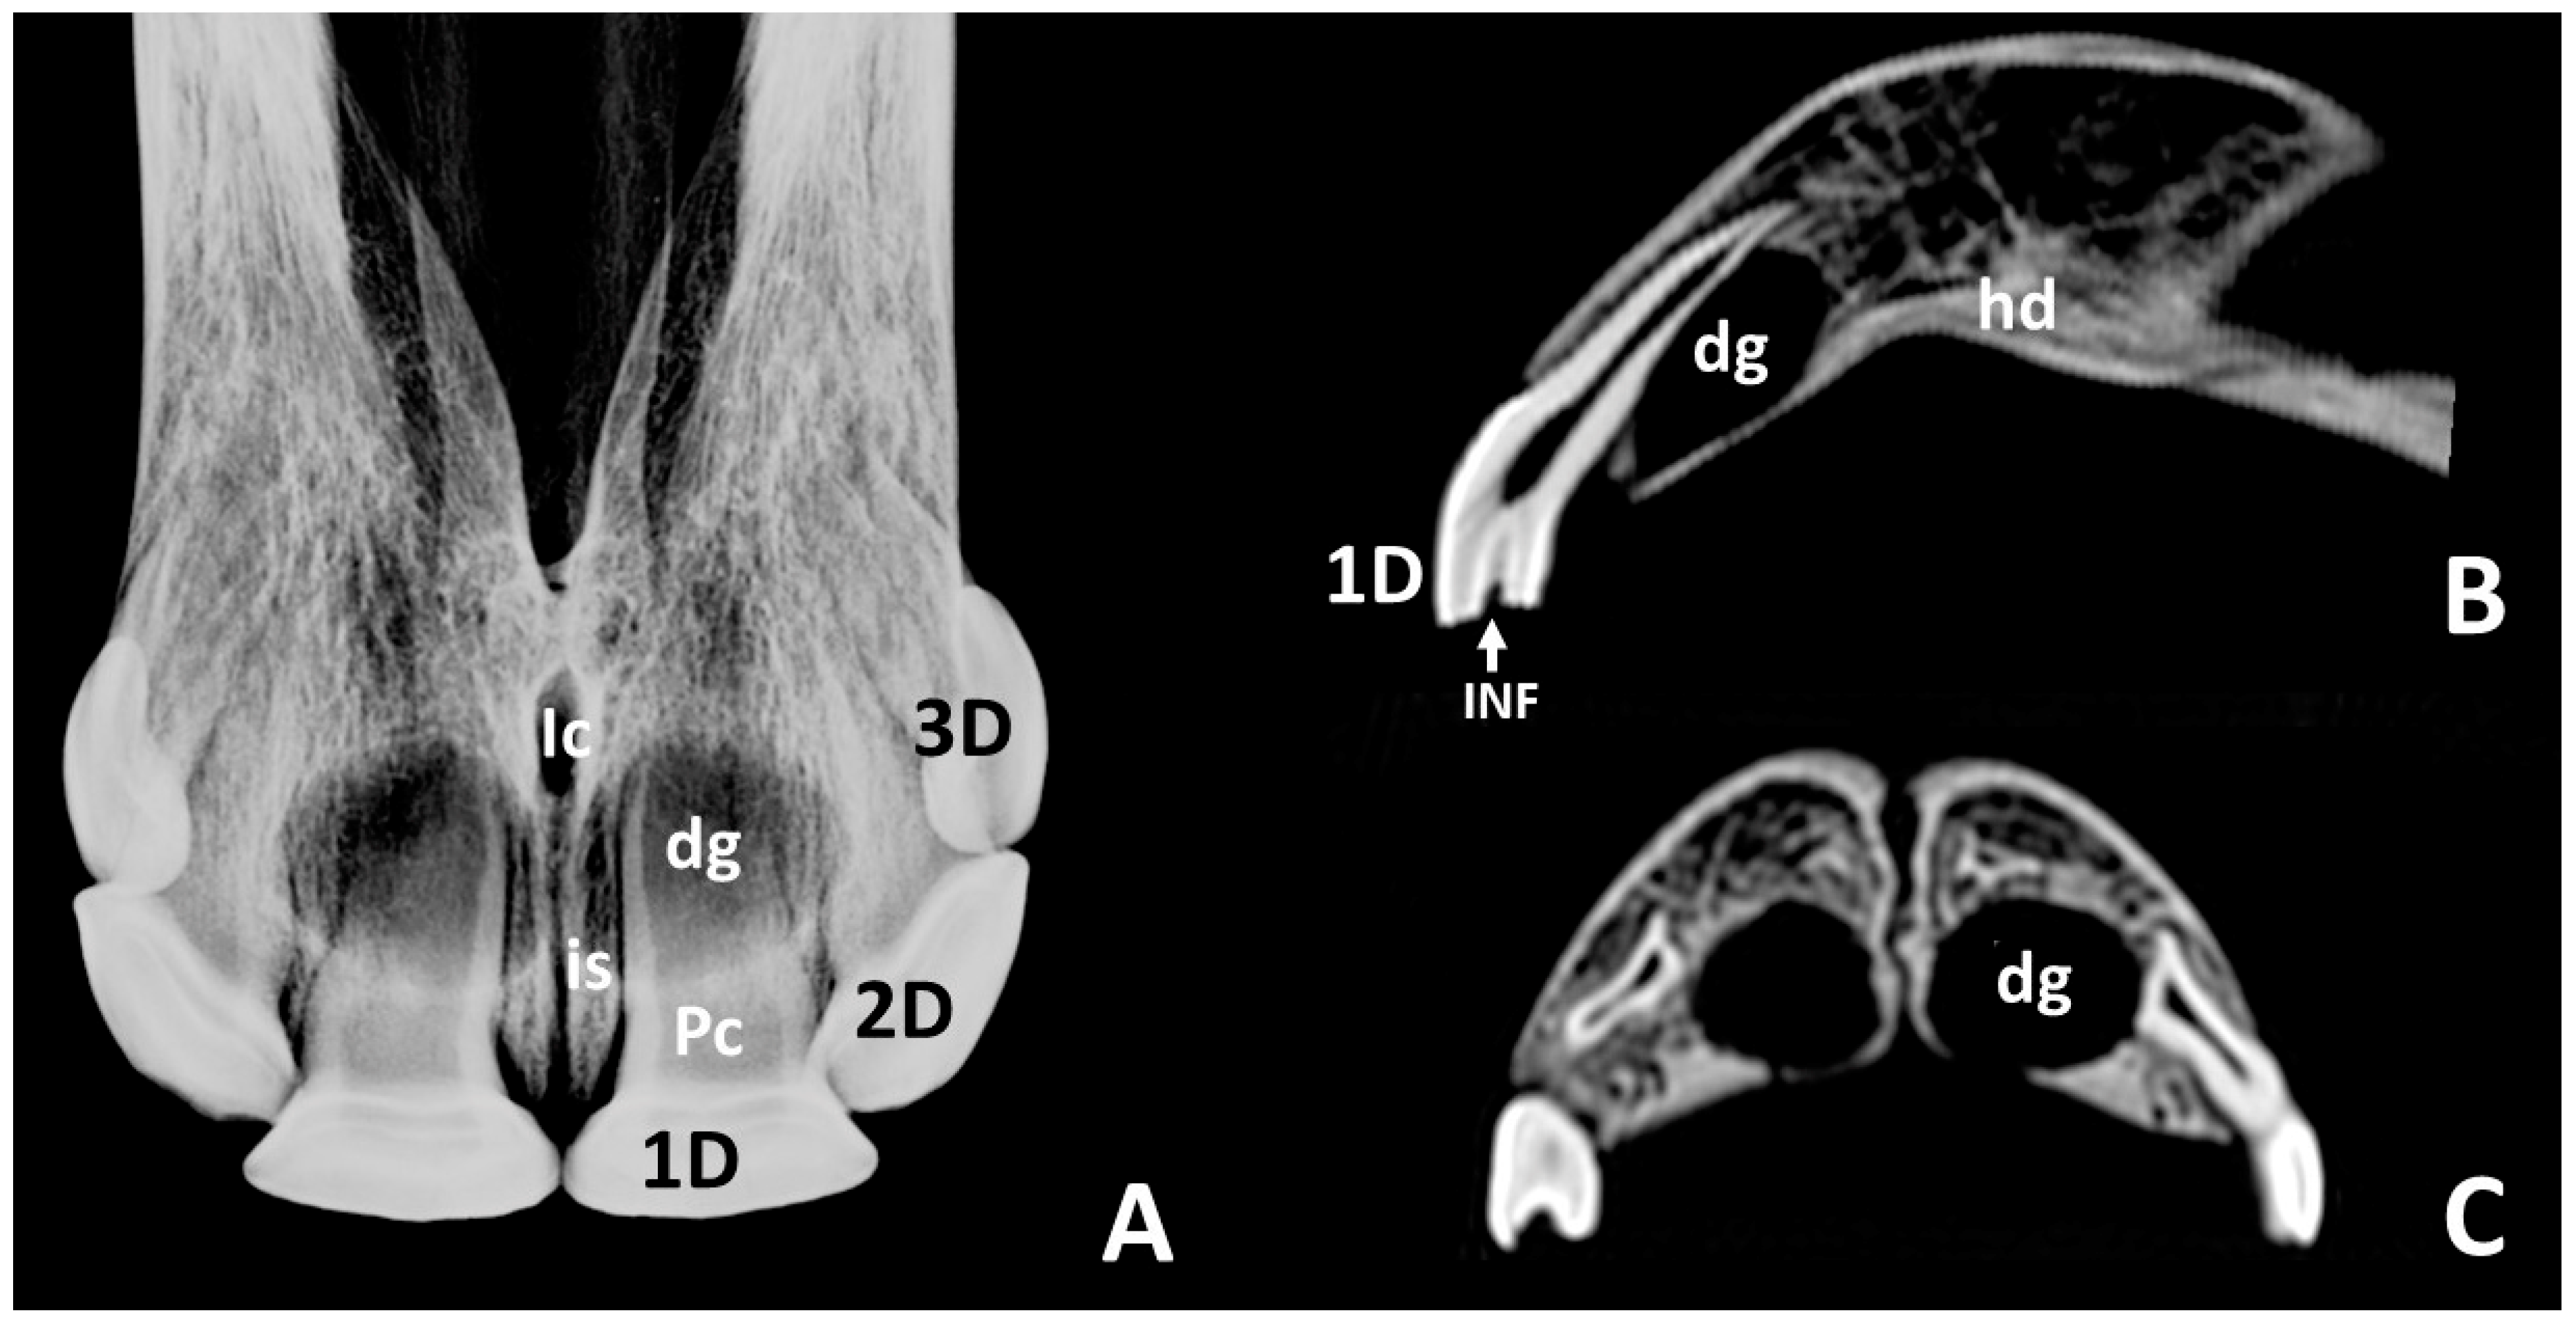

3.2. Radiographic and CT Studies

4.1. Deciduous Incisors: Radiographic and CT Studies

4.2. Permanent Incisors and Alveoli: Radiographic and CT Studies